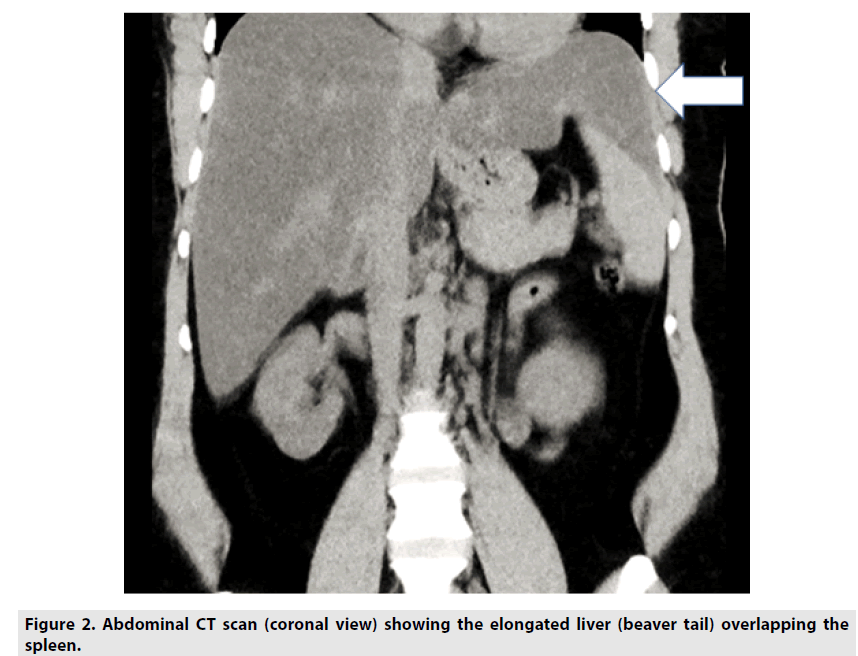

A 33 year old female diagnosed as Evan’s syndrome due to systemic lupus erythematosus (SLE), and lupus nephritis was further investigated for clinically enlarged liver and spleen [1]. The CT abdomen showed in addition to a mild hepato-splenomegaly, the presence of significant beaver tail liver (FIGURES 1 &2). Though this incidental finding is of a benign nature it yet has some clinical implications particularly in a patient like this one, who has thrombocytopenia (platelets of 86.000 mm3), and hemorrhage is a potential complication. In case of trauma or injury to left side of the abdomen, which classically affects the spleen, this liver elongation may be affected and can be mistaken for splenic trauma or hemorrhage. Furthermore, the associations of this liver variant with other conditions are rather rare in the literature, so its coexistence here with a case of SLE related Evan’s syndrome has some academic orientation as well.